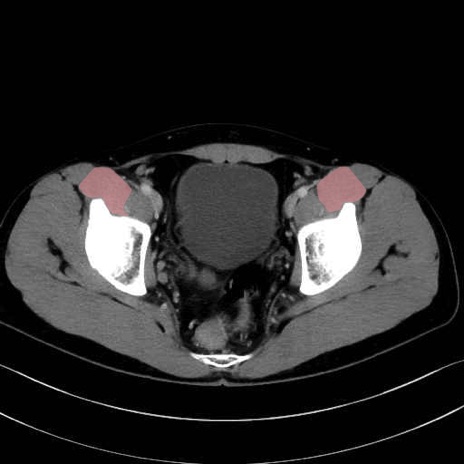

腸骨筋 (Iliacus)